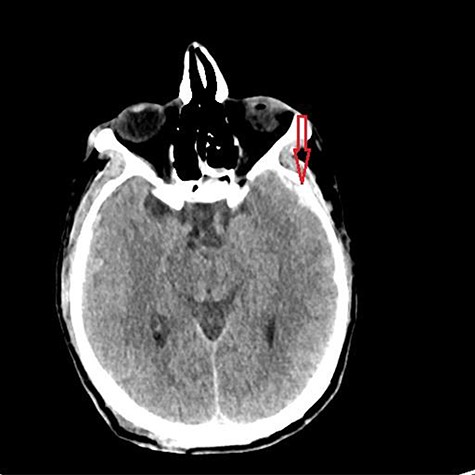

He was paralyzed, intubated and taken emergently to the OR due to nonresponsive hypovolemic shock. A right frontal ICP monitor was placed in the operating room while he was undergoing an emergency thoracotomy. Intraoperative ICP was in the 40s, and thus the patient was taken directly from the operating room to CT scan which showed enlargement of bilateral contusions, left greater than right, for which he was taken emergently to the operating room for a left hemicraniectomy (Figs 2 and 3).

CT head post thoracotomy with expansion of contusion with shift.